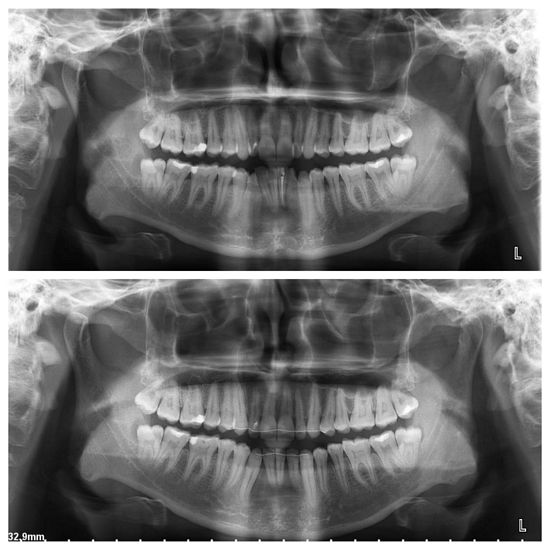

Malocclusion Type: Skeletal Class III and Dental Class I Malocclusion.

Mechanics: MBT Mechanics.

Treatment: Skeletal Class III Dental Class I Malocclusion with crowding in upper anteriors and anterior crossbite treated Non-surgically.